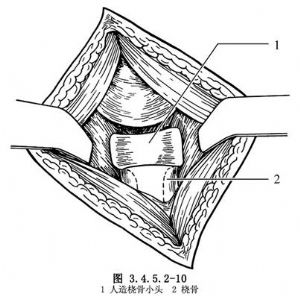

取肘關節後外側入路顯露並切除橈骨小頭。修平橈骨頸殘端,用髓腔擴大器將橈骨近端髓腔擴大,以適合人工橈骨小頭的柄部。然後將選定的人工橈骨小頭試行插入(圖3.4.5.2-10)。觀察其大小和接觸面是否合適。如合適,則試行活動肘關節和旋轉前臂,觀察人工小頭是否穩定。徹底止血後,縫合關節囊及各層組織。